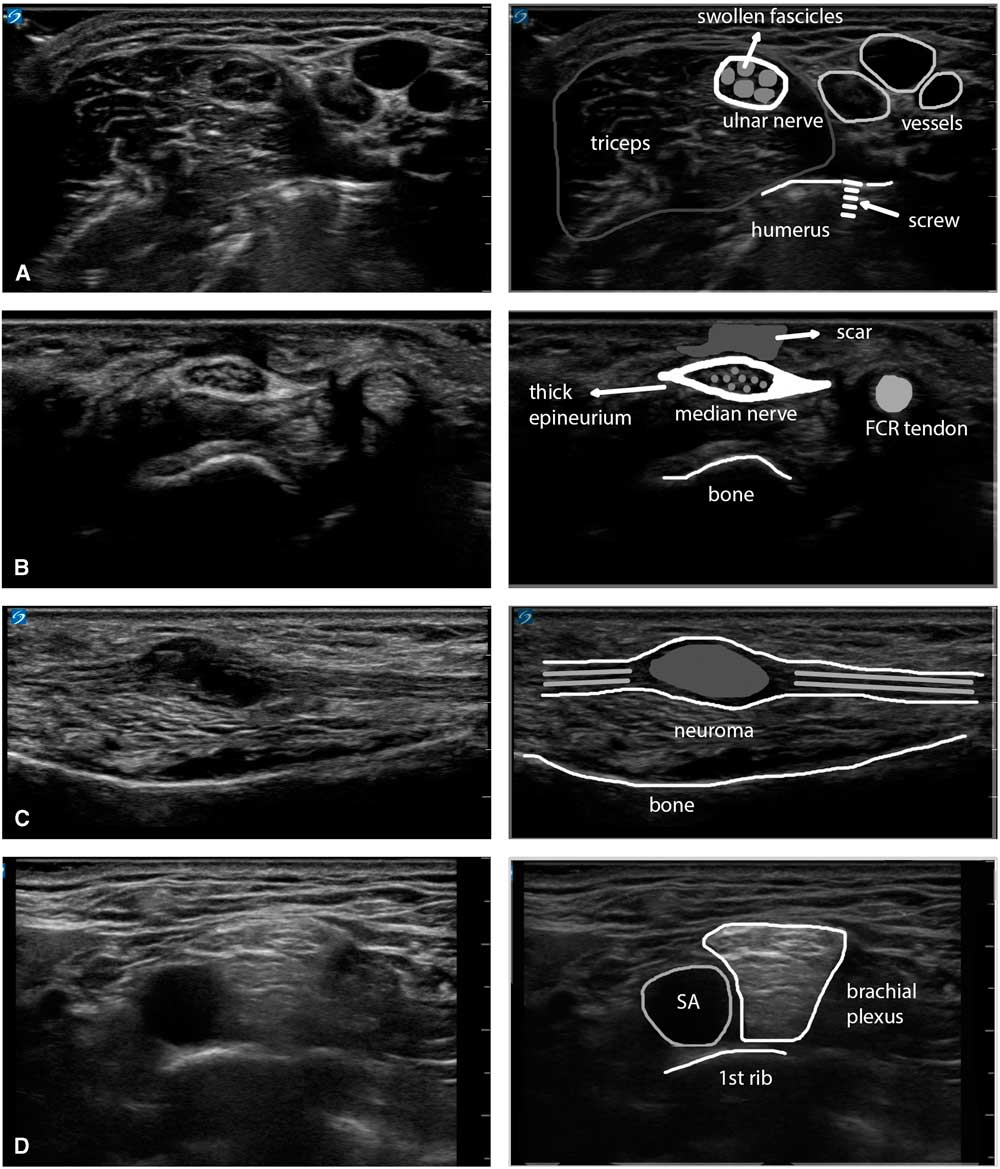

Visual evaluation of nerve appearance

In addition to quantifying nerve size, it is also informative to visually evaluate the appearance of the nerve and its fascicles.Reference Grimm, Winter, Rattay and Härtig 23 Nerves that have suffered mechanical compression or stretch, such as in entrapment or traumatic (or iatrogenic) traction injury, usually become swollen and hypoechogenic, and thus the CSA increases and the fascicles look more black at or just proximal to the site of pathology. With repeated mechanical friction, such as in long-standing carpal tunnel syndrome or ulnar neuropathy at the elbow, the nerve may form a very thick outer epineurial rim, giving the appearance of a thick white band surrounding the fascicles. Actively inflamed nerves—for example, in chronic inflammatory demyelinating polyneuropathy—can become grossly swollen and show fascicles with a diffusely grayish “ground glass” appearance, and a transected nerve will show two swollen stumps a few centimeters apart in a longitudinal image, with no recognizable nerve tissue in between. It is important to look for these associated changes in nerve appearance and capture them transversally and longitudinally for reporting (see Figure 8, e.g., of nerve pathology).

Figure 8 Panel showing four examples of the visual appearance of nerve pathology. (A) Swollen ulnar nerve in the upper arm with enlarged, hypoechoic fascicles and a slightly thicker epineurium, caused by thermal injury of the nerve during surgery for a humeral fracture (osteosynthesis material is visible in the underlying bony structure). (B) Enlarged median nerve at the wrist with a very thick epineurium and an overlying subcutaneous scar, caused by repeated carpal tunnel decompressions in the context of ongoing labor-induced compression of the nerve. (C) Neuroma in continuity of the ulnar nerve in the forearm after a glass-cut injury that partially transected the nerve and encased it in scar tissue (a Sunderland mixed-grade 4/5 lesion). (D) Supraclavicular brachial plexus lying on top of the 1st rib and adjacent to the subclavian artery in a patient with active chronic inflammatory demyelinating polyneuropathy. The different plexus elements are swollen and show a typical diffusely hyperechogenic appearance. FCR=flexor carpi radialis; SA=subclavian artery.